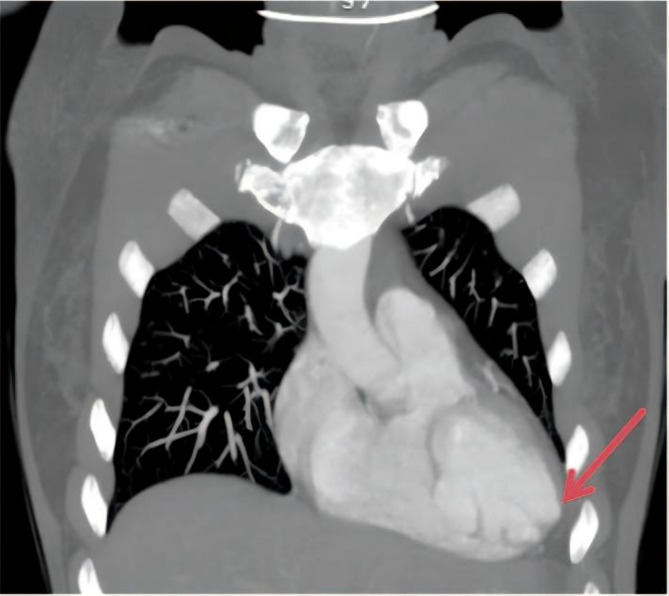

Background: Hypoparathyroidism (HypoPT) is a rare endocrine disease characterized by hypocalcemia, hyperphosphatemia, and insufficient or no parathyroid hormone (PTH) secretion. Hypoparathyroidism-induced chronic hypocalcemia may lead to cardiovascular complications, including myocardial dysfunction and arrhythmias. Interventricular septal dissecting aneurysm, a rare cardiac anomaly, typically arises following structural or ischemic heart disease. This disease can lead to ventricular septal rupture and aneurysmal cystic chamber formation, causing changes in cardiac structure and hemodynamics as well as giving rise to various heart complications.

Case presentation: No study has reported an association between hypocalcemia and cardiac masses. We encountered a case of hypoparathyroidism in a middle-aged woman who developed an interventricular septal dissecting aneurysm. Upon examination, we found that HypoPT has a profound impact on the heart.